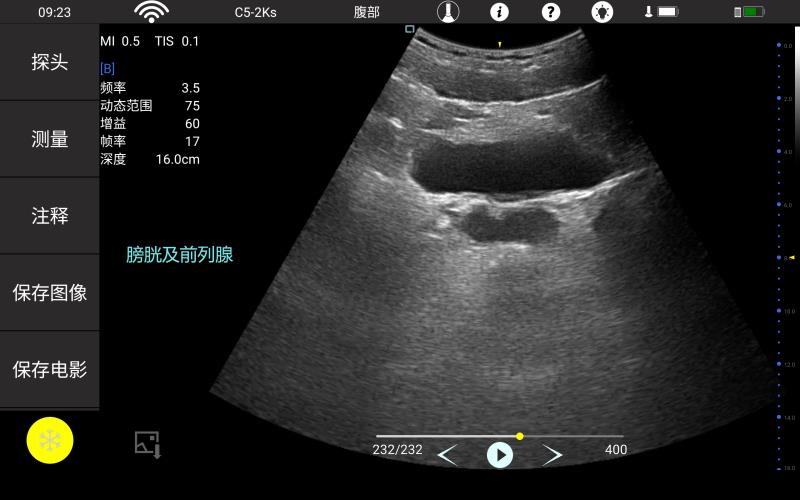

• 大凸

腹部

肾脏

妇科产科

心脏

肺等